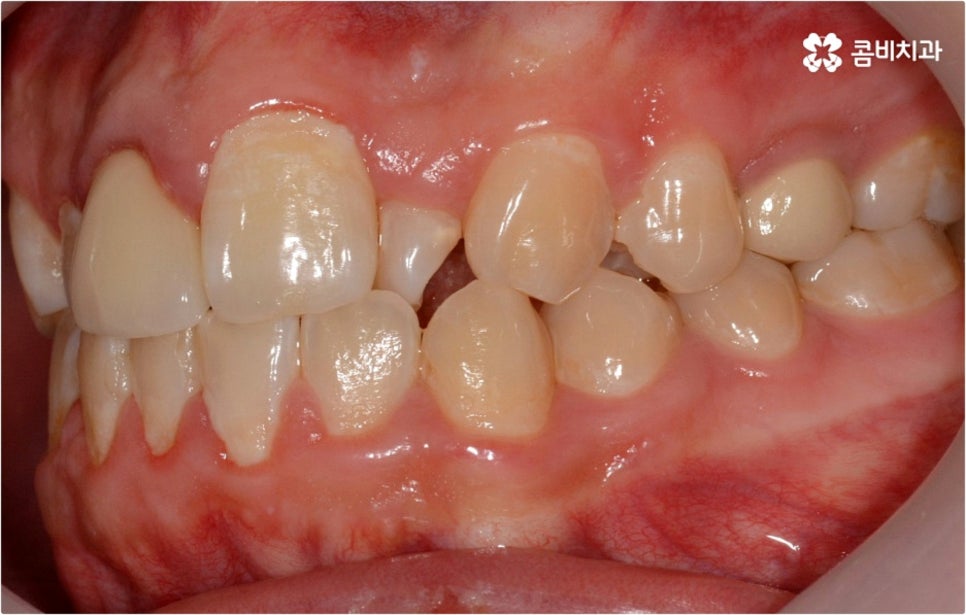

웃을 때 살짝 드러나는 덧니는 사람에 따라 매력 포인트로 느껴지는 경우도 있지만 구강 건강 측면에서 보면 치아와 치아가 겹쳐진 부분에 음식물 찌꺼기가 남아 치석이 쌓이기 쉽기 때문에 충치나 잇몸병이 더 자주 발생할 수 있으므로 주의하실 필요가 있습니다. 이와 같이 덧니는 옆 치아와 잇몸에까지 지속적으로 좋지...

출처 아카이브 열기웃을 때 살짝 드러나는 덧니는 사람에 따라 매력 포인트로 느껴지는 경우도 있지만 구강 건강 측면에서 보면 치아와 치아가 겹쳐진 부분에 음식물 찌꺼기가 남아 치석이 쌓이기 쉽기 때문에 충치나 잇몸병이 더 자주 발생할 수 있으므로 주의하실 필요가 있습니다. 이와 같이 덧니는 옆 치아와 잇몸에까지 지속적으로 좋지 않은 영향을 주기 때문에 개선해 주는 게 좋은데요, 특히 덧니의 개수가 많아 삐뚤빼뚤한 정도가 심하다면 교합이 잘 맞지 않아 씹기가 불편하거나 턱관절 압박, 통증 등을 유발할 수 있으며 나아가 안면비대칭으로 이어질 수 있기 때문에 방치하지 말고 될 수 있는대로 빨리 덧니교정 을 통해 이를 바로잡아 주시길 권유드리고 있습니다.

덧니교정 시 환자분들의 상황에 따라 치아 이동에 필요한 공간이 부족하지 않다면 비발치 교정이 가능한데요, 이런 경우 치아 사이를 살짝 갈아서 여유 공간을 만드는 치간 삭제 방법, 마지막 어금니를 후방으로 이동시키는 방법, 그리고 악궁 확장 장치를 사용해 치아 사이를 벌려주는 방법 등 다양한 방법으로 공간을 만들어 치열을 가지런하게 바로잡아 줄 수 있습니다. 이때 환자분들의 구강 상태, 즉 악궁 크기 대비 치아의 크기, 치아가 겹친 정도, 덧니의 위치와 개수 등을 자세하게 검진한 다음 치아가 이동할 충분한 공간이 확보되지 않는다면 발치 교정을 하게 될 거예요.

아마도 많은 분들이 치아를 뽑는다는 것에 대한 두려움을 가지고 있으시겠지만 그렇다고 해서 발치 교정이 필요한 케이스임에도 불구하고 치아를 뽑지 않고 진행을 하게 되면 치아 이동이 생각했던 것만큼 이루어지지 않기 때문에 결과에 따른 만족감이 떨어질 수 있어요. 특히 부정교합의 정도가 심각하고 골격적인 원인이 영향을 주고 있는 경우에는 발치 과정이 불가피 할 수 있으므로 의료진과 충분하게 상담을 하셔서 자신의 현재 상황에 따른 발치 교정의 필요성을 정확하게 이해하고 치료를 받으시길 권유드리고 있습니다.